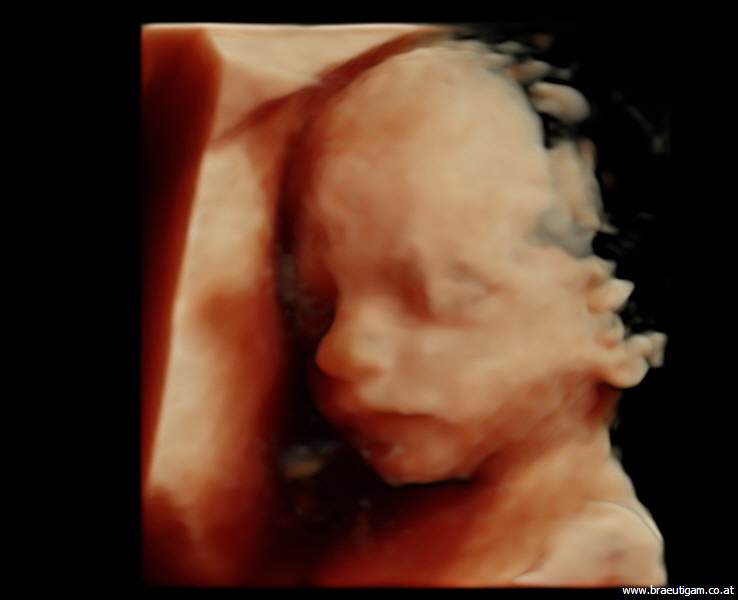

d.h. pränataler Ultraschall (Messung der Nackendicke, Organscreening) einerseits, andererseits kann noch eine Untersuchung mittels 4D-Ultraschall durchgeführt werden,

wo ein dreidimensionales Bild von Ihrem Kind angefertigt werden kann.

Dieses ermöglicht die Diagnostik einiger Fehlbildungen wie etwa der Lippen-Kiefer-Gaumenspalte, andererseits kann so das erste "Foto" von Ihrem noch ungeborenen Kind gemacht werden, was die Mutter-Kind-Beziehung zusätzlich fördert.